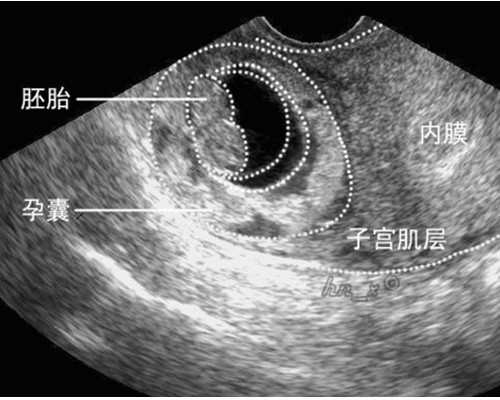

自然怀孕目前是没有什么较好的方法能预防22号染色体三体胚胎着床成功,但可以尝试去做三代试管婴儿,其可以对胚胎进行筛查,排除掉22号染色体三体胚胎和其他有异常的胚胎,移植健康的胚胎让其成功着床。一般胚胎22号染色体三体产生原因与精子卵子dna、药物、饮食感染、电磁波感染等有关,要预防只能从源头抓起。

正常情况下22号染色体应该是2条组成,胚胎22号染色体三体是一种染色体异常,也就是22染色体多了一条,属于染色体数量异常。目前临床上并没有很好的预防方法,只能通过以下方式尽可能的避免22号染色体三体胚胎着床成功: